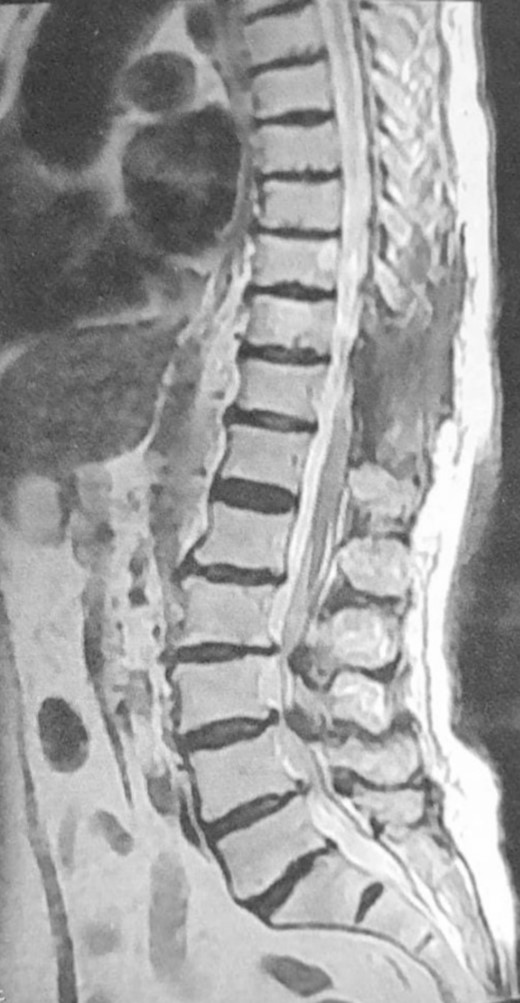

An otherwise healthy 80-year-old female patient presented with left lower extremity weakness following frequent falls ~1 month ago. Upon examination, motor power in the left lower limb was graded as III, accompanied by hypoesthesia. Without any other accompanying symptoms, magnetic resonance imaging (MRI) of the spine revealed a lesion within the vertebral canal causing compression of the spinal cord at the D10–D11 level (Fig. 1). T1-weighted images (T1WI) displayed hypointense calcified regions

Preoperative MRI, sagittal view, T2WI, shows tumor mass at levels D10–D11.

within the lesion, while T2-weighted images (T2WI) exhibited variable signal intensity, predominantly hypointense, in addition to surrounding tissue changes indicative of compression and edema (Fig. 2). Subsequently, the patient underwent surgical excision of the lesion, including laminectomy of D10–D11. A sharp dissection of the mass from the dura was performed during the surgery (Fig. 3). Two months after surgery, the patient underwent a short course of physiotherapy for several weeks, and now they can ambulate without support. The postoperative period was uneventful. Histopathological analysis revealed the presence of classical psammoma bodies, characterized by calcium deposits or punctate calcifications within the tumor mass, consistent with a diagnosis of classic meningioma ossified (Fig. 4). A follow-up MRI performed after 3 months demonstrated complete excision with no evidence of tumor recurrence (Fig. 5).